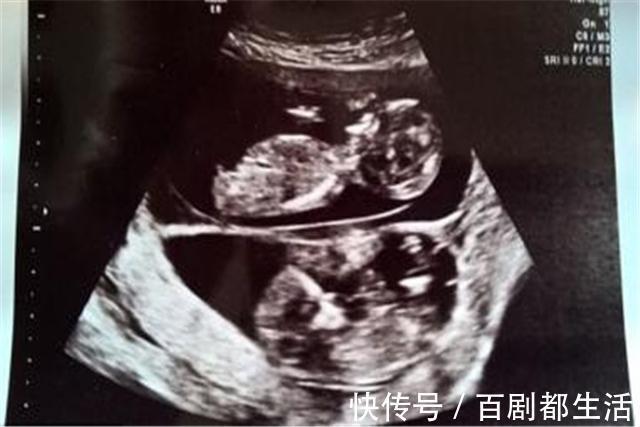

程先生是海归,他和妻子是通过相亲认识的,婚后不久妻子怀孕了,因为是双胞胎,这让婆家人很高兴,但随着孩子慢慢长大,程先生发现两个孩子不仅不像,小儿子也一点都不像自己,于是程先生带着孩子去做了亲子鉴定,结果证实小儿子与程先生没有血缘关系。一开始小程没多想,妻子也觉得是护士抱错了,于是一家人闹到了医院,结果医生的话让程先生暴怒,医生说:“两个孩子应该是异卵双胞胎,你妻子应该是在受孕后的48小时内与别的男人发生了关系,她狡辩不了。”

准妈妈在排卵时,非常巧合的同时排出两个卵子,正常情况下是一个,这两个卵子同时和准爸爸的两个精子结合。于是,准妈妈的子宫里就出现了两个受精卵,这样出来的双胞胎就不会像,甚至差距很大,但有一点,那就是同血缘。

这个说法很好理解,是指孕妇在受孕后24小时至48小时内,再次进行性生活,导致体内再次受孕,于是就出现了怀有两个胎儿,假如后者是别的男人,两个孩子肯定是没有血缘关系的,这种例子还是很常见的。

和上面道理相同,妈妈在同一个经期周期内出现了两次排卵活动,如果和丈夫多次同房,恰好每次都有受孕的情况,那就会出现异卵双胞胎的情况,这样孩子虽然长的不像,但确实是一个父亲。

很明显,程先生妻子就是同期复孕,但是第二次怀孕就很毁三观了,否则也不会出现没有血缘关系一事。我们常见的双胞胎都是同卵双胞胎,是由一个受精卵分裂成两个胚胎,所以宝宝们出生后在外表上极为相似,而且能保证双胞胎是同父同母的只有同卵双胞胎,而异卵双胞胎就存在其他可能性。所以说出现类似情况大家不要总觉得是医院的责任,去问问你们妻子吧。